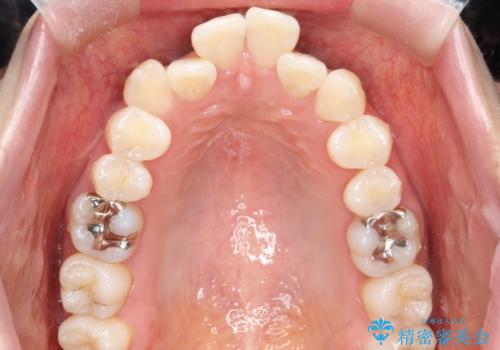

- 出っぱによる口元の閉じにくさを主訴に来院されました。上顎の出っ歯と上下顎叢生も認められたため、上下顎両側4番抜歯を行い、ワイヤー矯正で治療する治療計画を立てました。

上顎にはMI(マイクロインプラント)を埋入して固定源とすることで出っ歯の改善を図りました。

少しスペースクローズに時間がかかりましたが、MIを用いたワイヤー矯正で

主訴である出っ歯と叢生が改善されました。口も閉じやすくなり、スッキリとした口元になりました。